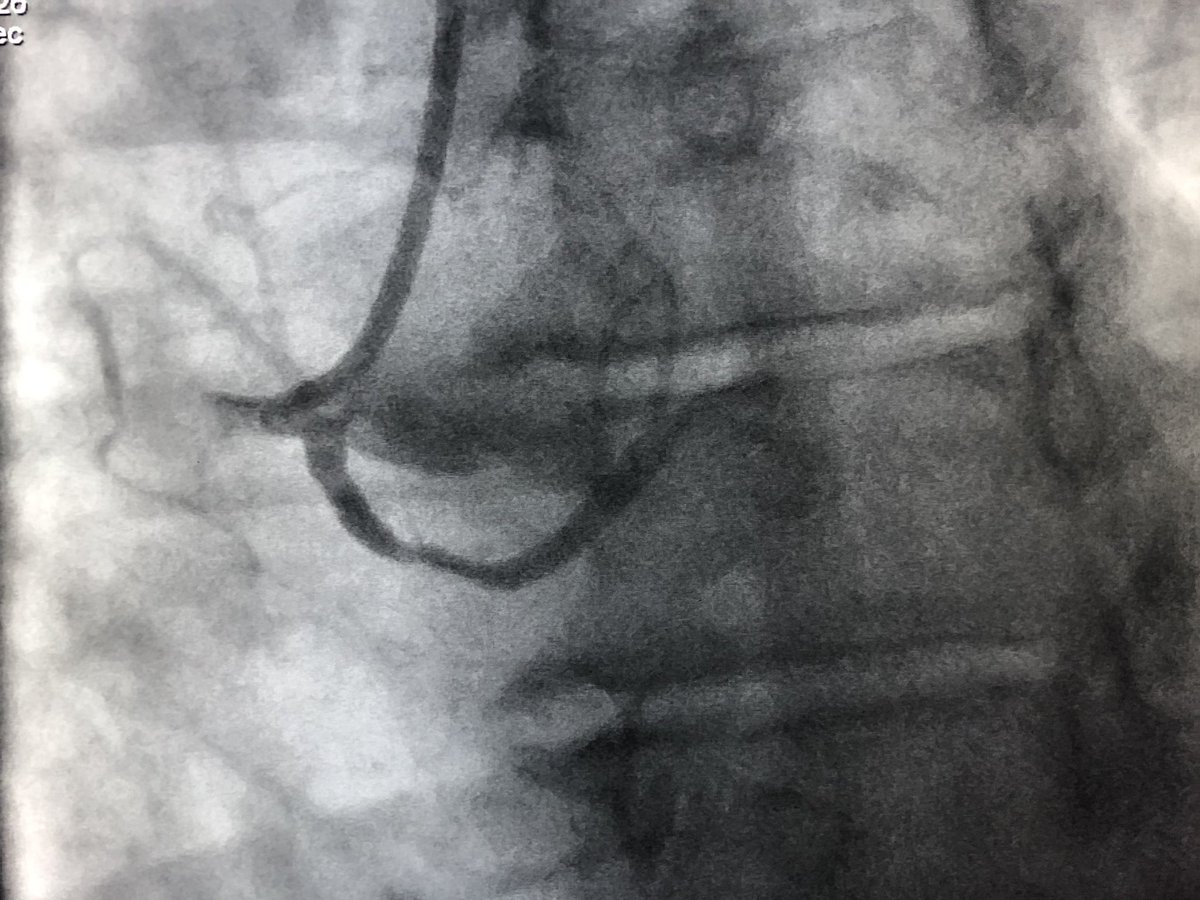

Hypothetical pt - mid 60’s w angina - multi-vessel dz including 🔹RCA CTO J -CTO score 2 🔹 All non-CTO lesions fixed (angina resolves) 🔹EF 60% 🔹high volume CTO center ❓What to do for RCA CTO @TAVRBot @RadialFirstBot @mmamas1973 @jtsaxon @djc795 @JAG24851 @DrBillLombardi